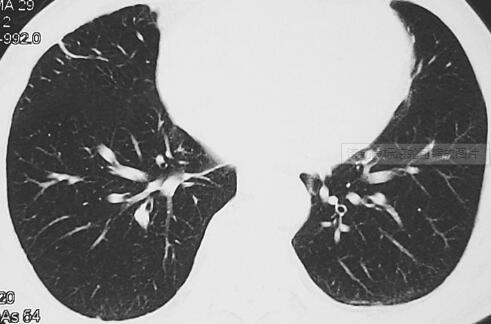

因病情逐渐加重转至上级医院,查HIV、乙肝都为阴性,查血培养阴性,查腹部B超提示肝稍大、回声增粗,查CTPA未见肺栓塞征象,查胸部HRCT可见双肺多个结节病变(图2)。

图2 胸部CT示双肺多个结节病变